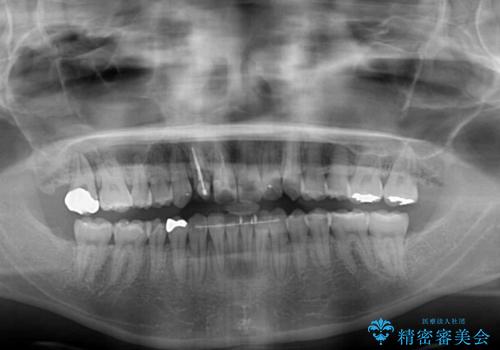

狭い上顎骨を拡大 インビザラインによる非抜歯矯正

上下の骨幅を改善したことで、スムーズに歯列矯正を行うことができました。

奥歯の咬み合わせを改善する必要があったため、治療は長期化しましたが、きっちりと仕上げることができました。